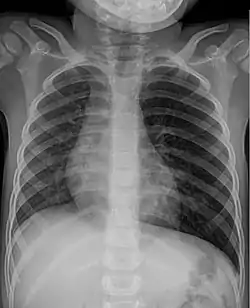

![]() تصوير الصدر بالأشعة السينية للطفل بعد رشف الفول السوداني: تضخم شديد في الرئة اليسرى بسبب آلية سد الفول السوداني في الشعب الهوائية تصوير الصدر بالأشعة السينية للطفل بعد رشف الفول السوداني: تضخم شديد في الرئة اليسرى بسبب آلية سد الفول السوداني في الشعب الهوائية | |